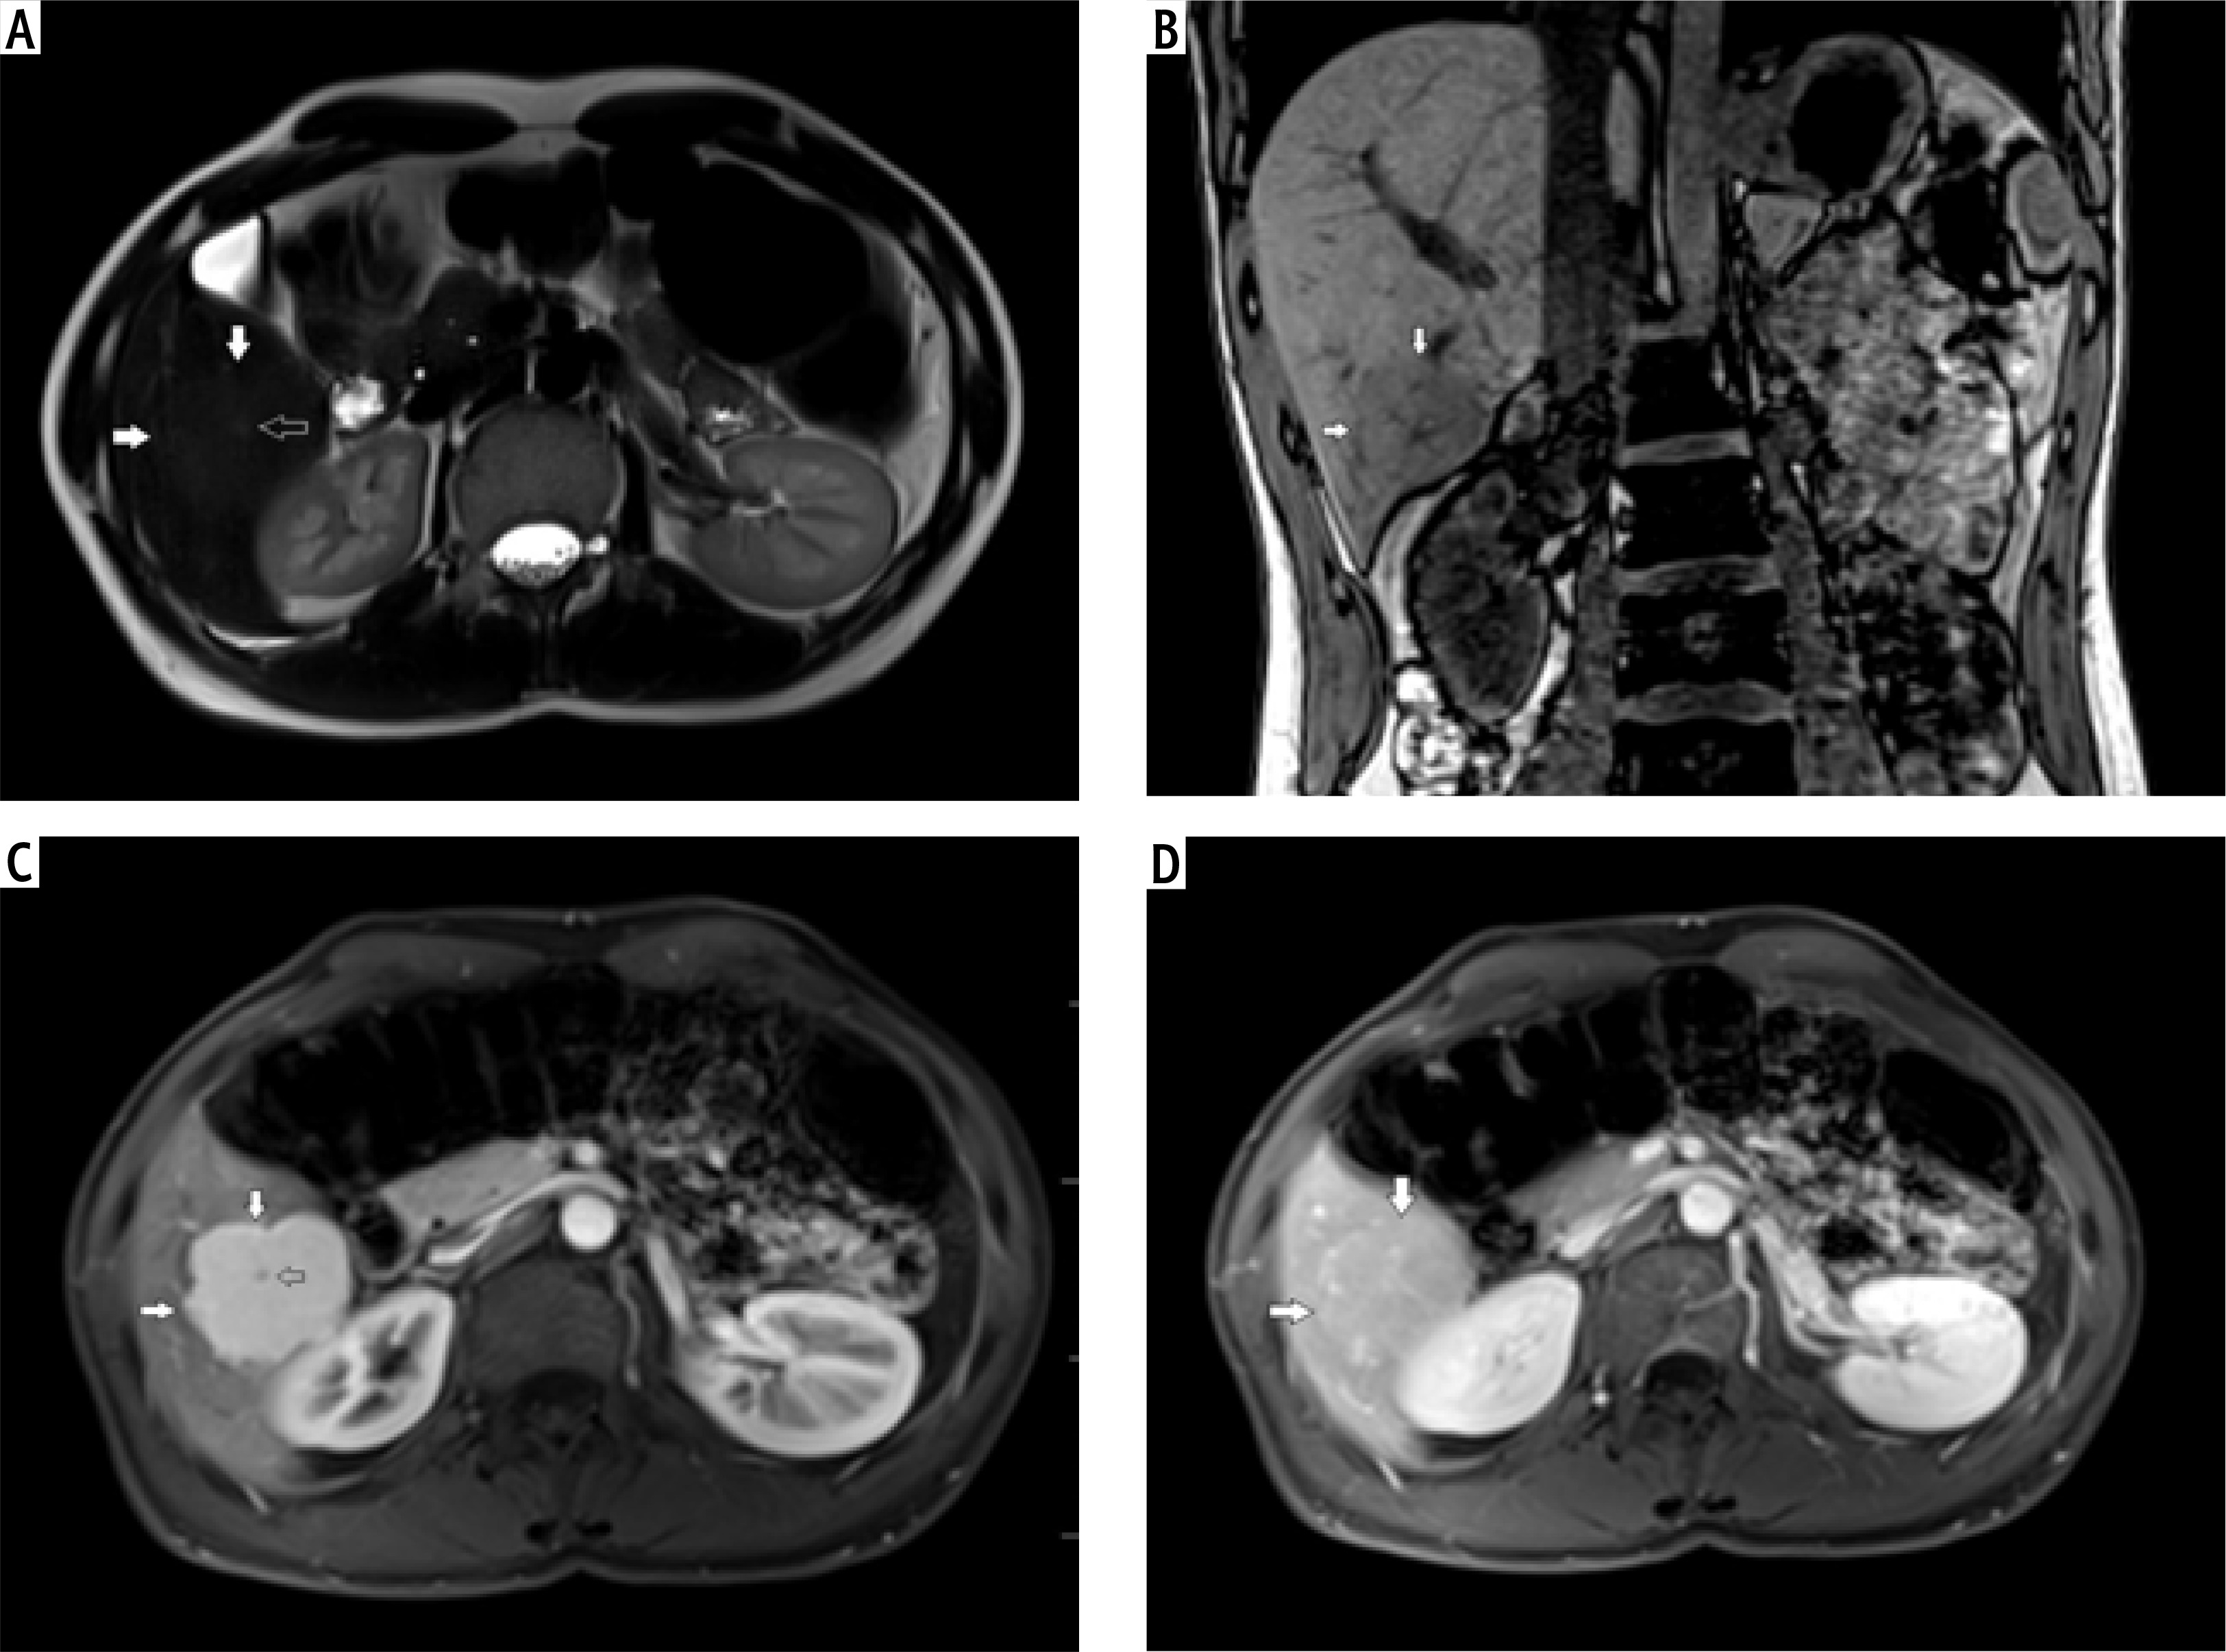

Fig. 2

A) T2-weighted image in transverse plane, focal lesion in the right lobe of the liver (full white arrows). Signal of the lesion slightly higher in relation to the liver parenchyma. B) T1-weighted image in coronal plane. Focal lesion in right lobe of the liver (full white arrows). The signal of the lesion is lower in relation to the liver parenchyma. In this sequence, the heterogeneity of the signal within the lesion is clearly visible. C) T1-weighted image in the early phase after administration of a contrast agent. Acquisition in the transverse plane. Focal lesion in the right lobe of the liver (full white arrows). The lesion enhances intensively in relation to the liver parenchyma. D) T1-weighted image in the late phase after administration of a contrast agent. Acquisition in transverse plane. Focal lesion in the right lobe of the liver (full white arrows). Enhancement of the lesion and the parenchyma of the liver in this phase is similar. The lesion was classified as hepatocellular adenoma (HCA)